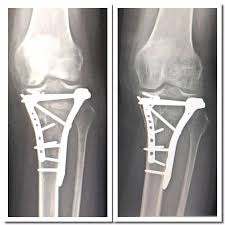

Here is more about these types. Tibial plateau fractures can be divided into two different categories non displaced and displaced tibial plateau fracture. For a period of about 6 8 weeks after the surgery you will be nwb non wait baring this means that you can not put any pressure on your knee and leg and will need to use a wheelchair crutches or both. Types of tibial plateau fracture.